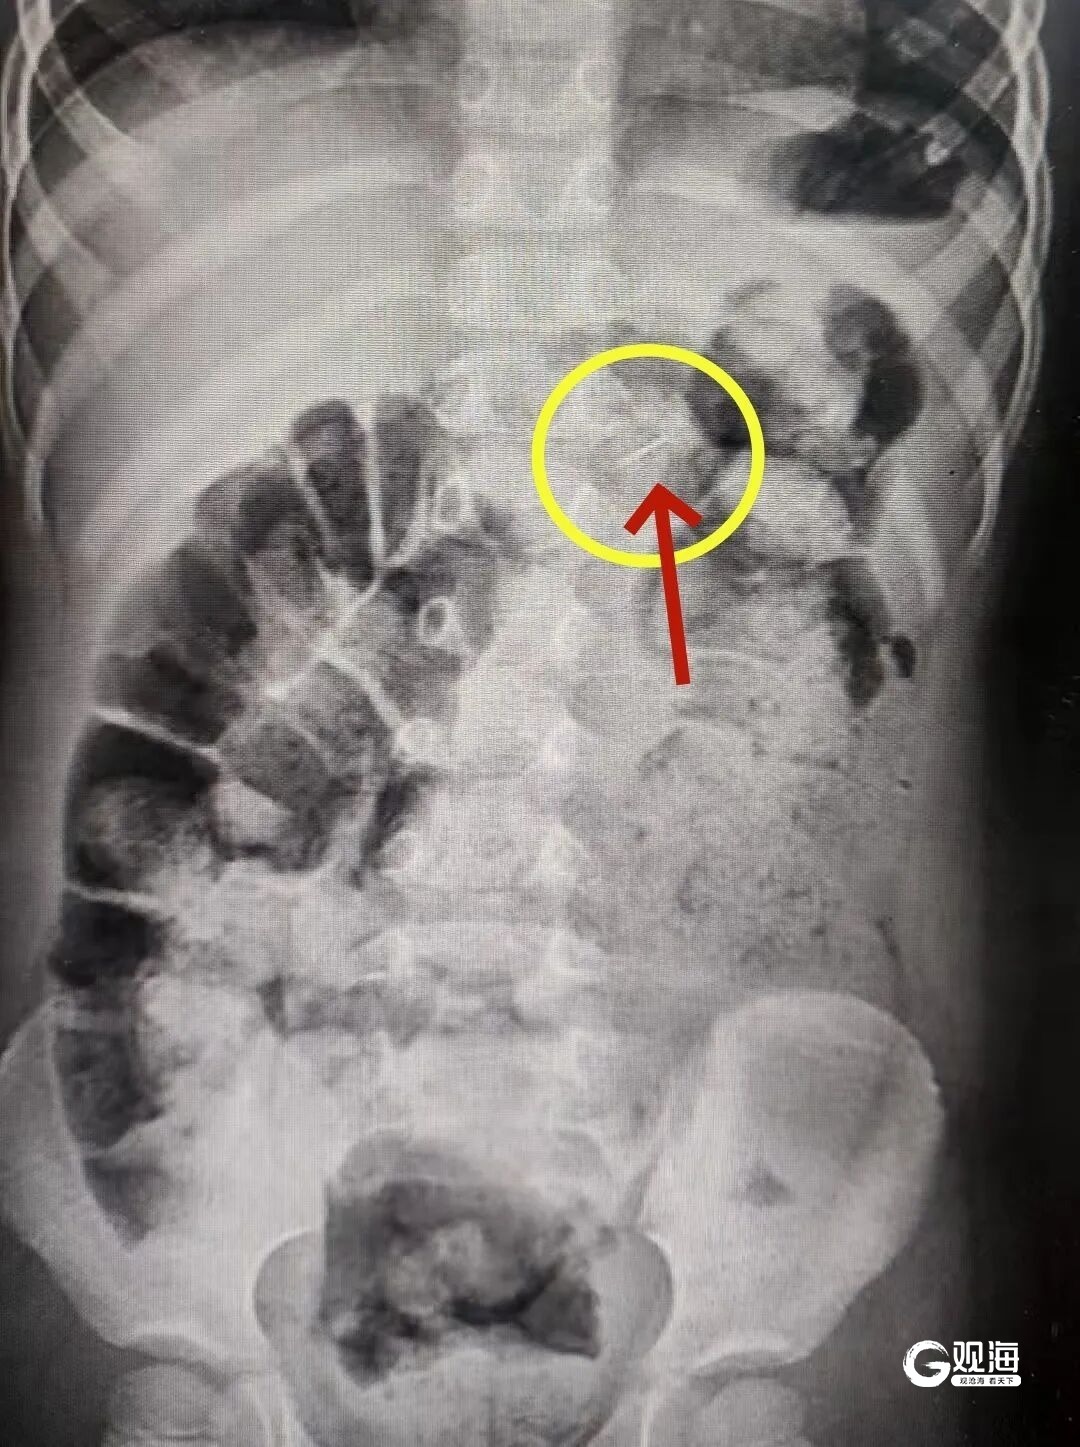

接诊医生高度警惕,第一时间安排影像学检查。片子清晰显示胃内有一枚针状异物。

急诊科医生紧急联系消化内科医生进行进一步的判断:胃肠粘膜很薄,肠壁也很薄,尖锐断针可能会随着胃蠕动进入肠内导致穿孔。情况危急,必须连夜手术取出。